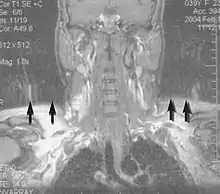

Angiography

Magnetic resonance angiography (MRA) generates pictures of the arteries to evaluate them for stenosis (abnormal narrowing) or aneurysms (vessel wall dilatations, at risk of rupture). MRA is often used to evaluate the arteries of the neck and brain, the thoracic and abdominal aorta, the renal arteries, and the legs (called a "run-off"). A variety of techniques can be used to generate the pictures, such as administration of a paramagnetic contrast agent (gadolinium) or using a technique known as "flow-related enhancement" (e.g., 2D and 3D time-of-flight sequences), where most of the signal on an image is due to blood that recently moved into that plane (see also FLASH MRI).[51]